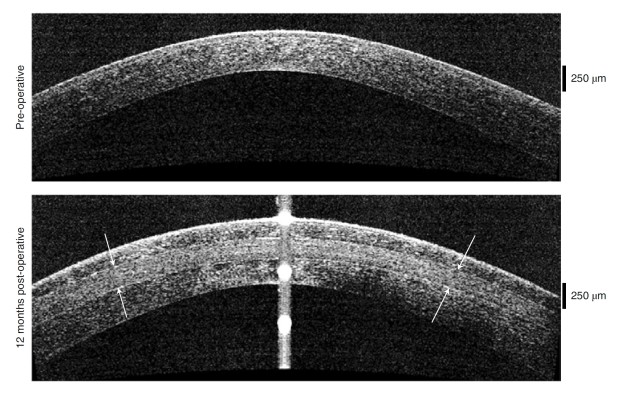

Promene u debljini i obliku rožnjače pre i posle usađivanja implanta

Implant ispravlja rožnjaču i vraća joj debljinu čime se ponovo uspostavlja mogućnost oka da se fokusira.